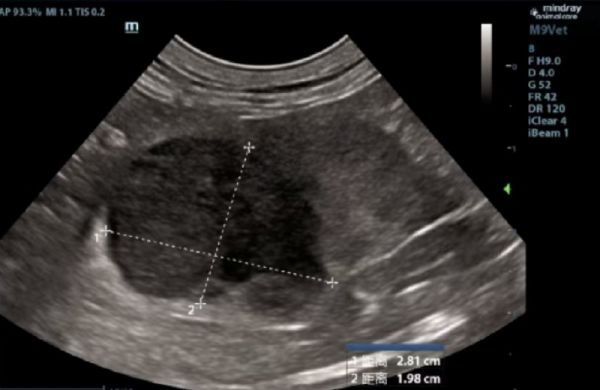

此前,一只8岁的猫咪因食欲下降、体重减轻就诊,经超声检查发现腹腔内有两处明显肿块,因肿物位于肾脏且猫咪体况较差,直接开腹进行病理检查损伤较大,石晶院长根据临床经验建议主人进行细针抽吸、血液检查等。细胞学检查确诊为肾脏淋巴瘤。随即进行化疗治疗,治疗后肾脏内肿瘤大小明显好转。